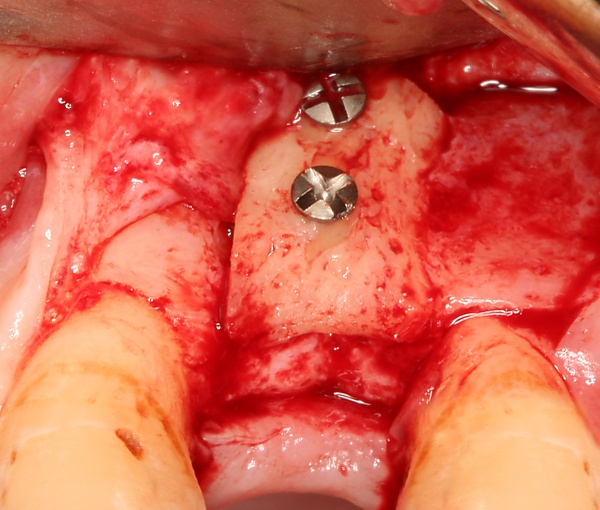

Разборный имплантат состоит из непосредственно имплантата и надстройки (супраструктуры), именуемой абатментом. Такой имплантат может быть установлен по одно- и двухэтапному протоколу. Двухэтапный протокол подразумевает полное погружение имплантата и накрывание его слизистой оболочкой, в результате чего исключается любой контакт имплантата с полостью рта — эта процедура называется первым этапом дентальной имплантации. Второй этап заключается в установке какой-либо надстройки (супраструктуры) — это может быть как формирователь десны, так и абатмент с временной коронкой или другим видом протезной конструкции. После какого промежутка времени будет выполнен второй этап обычно решает имплантолог, опираясь на данные о качестве костной ткани, возраст и общее состояние пациента, а также свой клинический опыт. Классические сроки составляют 4—6 месяцев, однако последнее время существует тенденция к сокращению сроков ожидания до 2,5—3 месяцев. Это связано с лучшим пониманием процесса остеоинтеграции, а также оптимизацией макродизайна и микрохарактеристик поверхности имплантатов.

Под термином «имплантация зубов» в стоматологии понимают только вживление зубного имплантата. В дальнейшем на вживлённый имплантат с помощью цемента крепится коронка, которая может быть временной — пластмассовой, металлокерамической, керамической, золотой и т. д. Относительно кости она должна располагаться на том же уровне, на котором ранее располагалась коронка зуба, замещаемого имплантатом. В практике чаще всего применяются два вида фиксации коронок на имплантаты: цементная или винтовая.